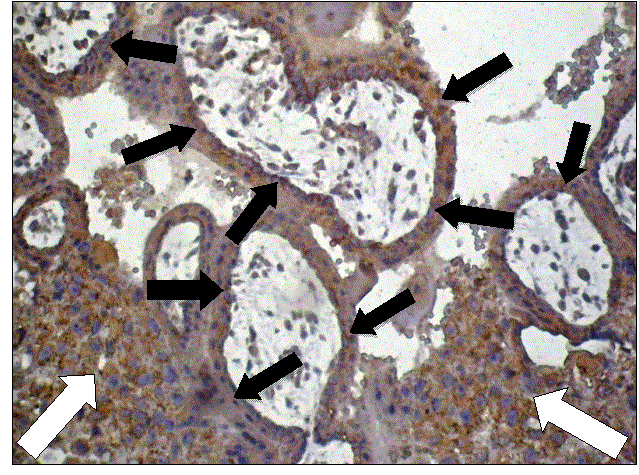

Результати забарвлення при застосованій імуногістохімічній методиці проілюстровані за допомогою рисунку 1.

Використання методу зондової комп’ютерної мікроденситометрії на цифрових копіях зображення дало наступні результати. Оптична густина специфічного забарвлення на фермент «металопротеїназа-2» в інвазивному цитотрофобласті у жінок з нормальним гормональним статусом становила 0,324±0,0023 умовних одиниць оптичної густини, а при гіперандрогенії – 0,208±0,0019 умовних одиниць оптичної густини (вірогідність розбіжності p<0,001). Оптична густина специфічного забарвлення на фермент «металопротеїназа-2» у трофобласті хоріальних ворсинок у жінок з нормальним гормональним статусом оцінена із середніми параметрами 0,209±0,0018 умовних одиниць оптичної густини, а у жінок з гіперандрогенією - 0,204±0,0017 умовних одиниць оптичної густини (розбіжність невірогідна – p>0,05). Слабка позитивна імуногістохімічна реакція на фермент «металопротеїназа-2» відмічалася також у стромальних клітинах хоріальних ворсинок (Рис.1), однак вимірювання інтенсивності забарвлення в цих клітинах не входило в задачі даного дослідження.

Рис. 1. Мікрофотографія. Інвазивний трофобласт (білі стрілки) та хоріальні ворсинки (чорні стрілки вказують на трофобласт хоріальних ворсинок) при гіперандрогенії. Слабке позитивне імуногістохімічне забарвлення відмічається також у стромальних  клітинах хоріальних ворсинок. Імуногістохімічна методика на фермент «металопротеїназа-2» з дофарбуванням ядер гематоксиліном. Об.20х. Ок.10х.